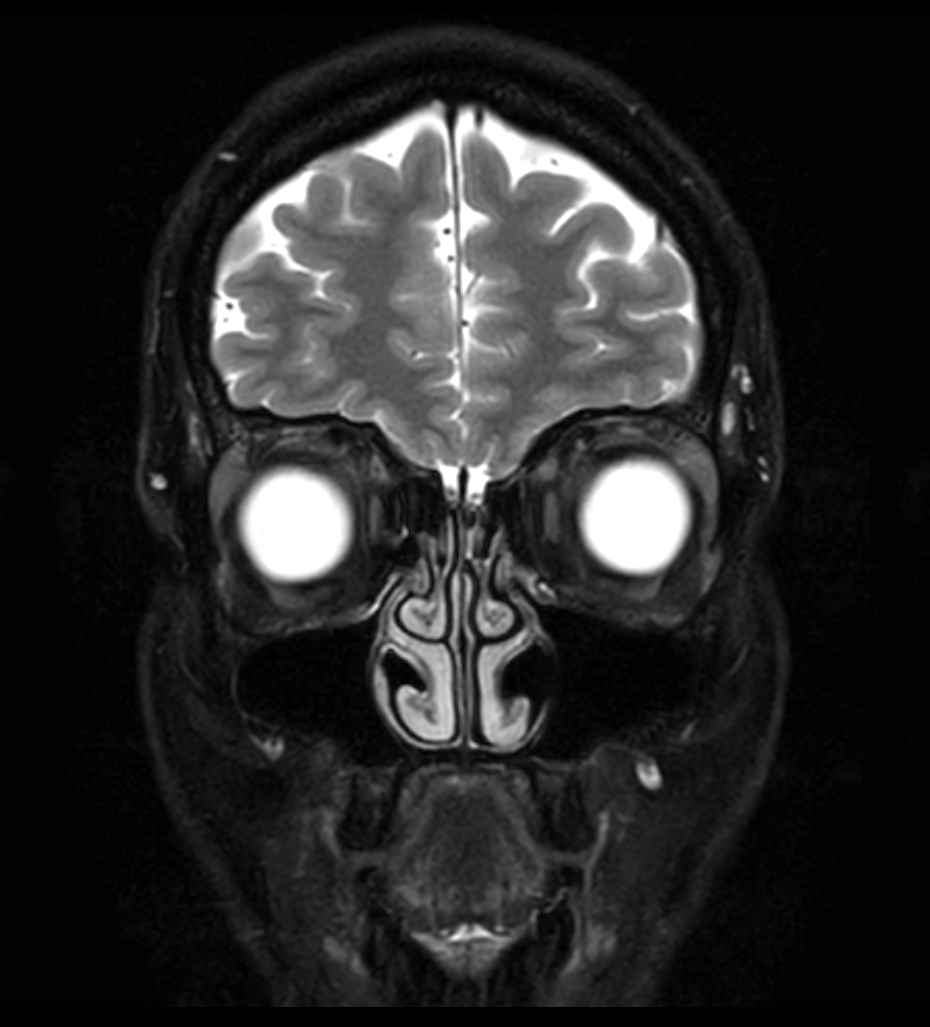

T2w TSE - MultiVane XD